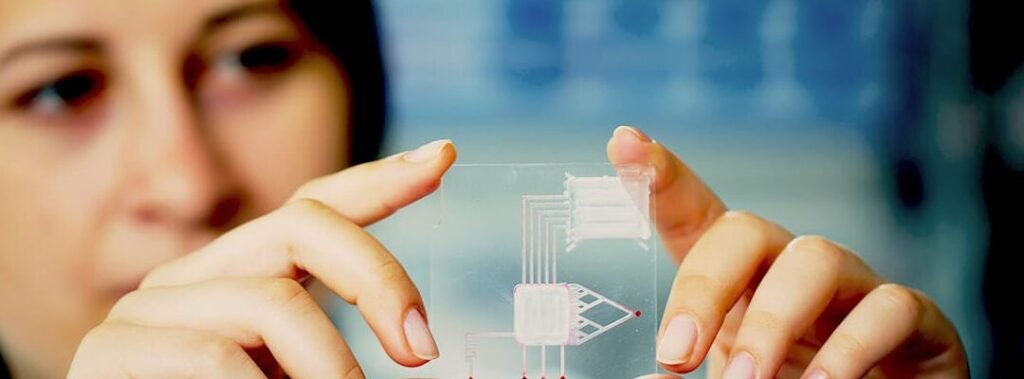

La representa un avance revolucionario en la medicina moderna, al integrar diagnóstico y tratamiento en un único...